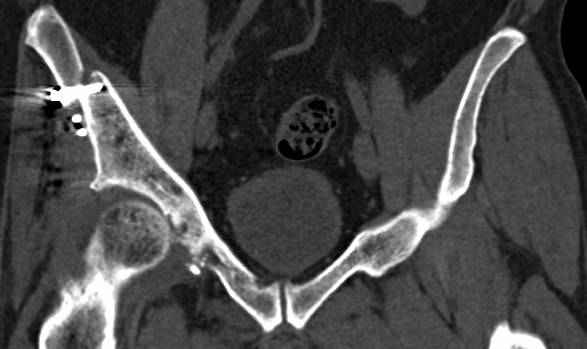

высылаю дополнительно сканы.

Судя по представленным реконструкциям (не очень хорошего качества - много наводок)

мы имеем дело с полупоперечным переломом у которого отломался задний край или его отломали, превратив перелом в полный двухколонный.

По отдельным срезам и тем более по реконструкции трудно судить о сращении крыла и задней колонны с осевым скелетом.

В большинстве случаев при двухколонных переломах

в итоге получается прочный бублик с дыркой. При эндопротезировании в дырку помещается головка, а чашка должна неплохо заклиниться в бублике.

Главное, чтобы бублик не был разорван, что не очень понятно на представленных снимках.

Поэтому хотелось бы дообследовать больного (разумеется включив стандартные проеции judet,и срезы показывающие сращение)